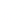

MRI 6 months after cartiform